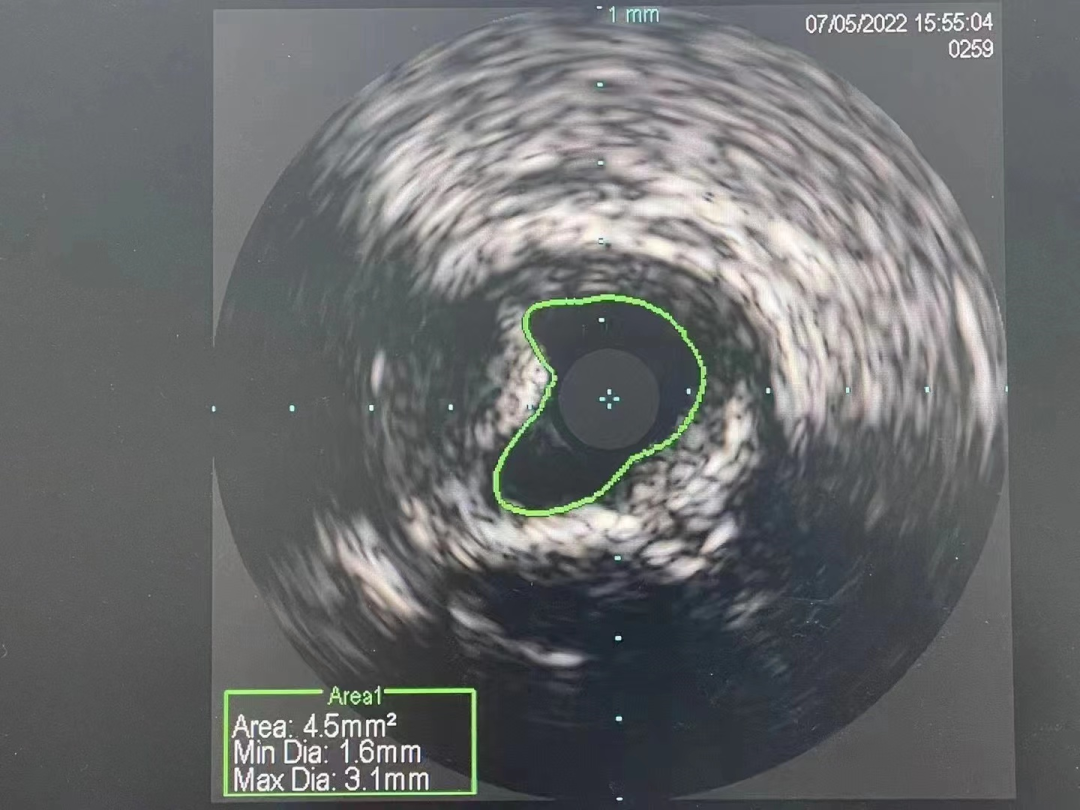

冠脉内介入治疗